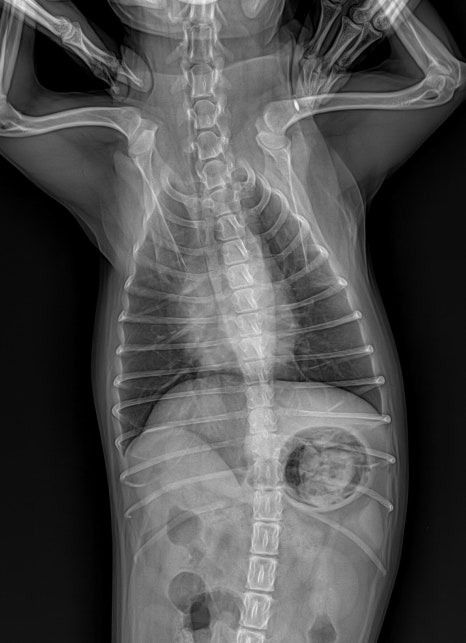

▪️ 흉부 X-ray 검사

심장 크기와 폐 상태, 만성 호흡기 변화 여부를 확인해 마취 중 호흡·순환 안정성을 판단합니다.

환자 흉부 방사선 사진/ 출처: 라온동물메디컬센터